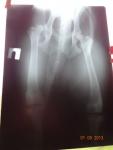

Увидев собаку, доктор Ягников сразу обратил внимание на неправильную походку и становление задних лап и предложил сделать рентген не только передних лап ( что впрочем мы уже подспудно ожидали ). Через 30 минут мы услышали диагноз. Он стал для нас шоком.

ПЕРЕДНИЙ локтевой сустав- локтевой отросток с трудночитаемым названием ( не пишем, боясь ошибиться в правильности написания -уточнить можно в скане диагноза в приложении к этому письму) требующий удаления.

Но это еще не самое страшное. ДИСПЛАЗИЯ ОБЕИХ задних лап, причем в очень серьезной стадии, одна из них практически на грани вывиха. ( в приложении- снимки рентген).

Итог озвученный доктором Ягниковым- «это ГЕНЕТИЧЕСКИЙ БРАК, собаку нужно вернуть заводчику, т.к. вам продали нездорового щенка. Дисплазия не лечится. В противном случае ( если вы захотите оставить щенка) вас в ближайшей перспективе ждут операции на трех лапах ( и может быть на задних придется делать повторные с вживлением металла в сустав) и долгое восстановление, антибиотики, таблетки и т.д. Нагрузки будут запрещены. Ни о каких выставках речи не идет. О размножении ( кабель же!) можно также забыть». Мы в шоке!!!! Слезы, нервные дни-вечера…Кто знает- тот поймет..

В течении месяца мы не могли принять решение. Прочитали кучу литературы на эту тему… И поехали к другому врачу. В этот раз к еще одному известному доктору- Еремину Д.А. ( хирург высшей квалификации, травматолог, ортопед, стаж 20 лет). Реакция один в один- только увидел щенка, сказал- тут проблема в задних лапах. Потом посмотрел снимки. ГЕНЕТИЧЕСКИЙ БРАК. Честно сказал: «я могу на вас заработать, ведь здесь будут операции и ни одна, потом трудное восстановление (постоянные антибиотики и таблетки что плохо повлияет на пищеварение, а у нас оно и так никуда не годное) т.к. собака вырастет 50-60 кг- это не шутки. С такой массой и такими лапами предсказать что-то невозможно. Но я бы собаку вернул. Понимаю жалко, но это будет правильно. На наш вопрос что будет через 10 лет- «о каких 10 лет идет речь, после операций и на таблетках- максимум 7».

Чуда как и ожидалось не произошло. Ситуация только ухудшилась. Что видно из снимков ( в приложении ). Дисплазия не исчезла, что и следовало ожидать.